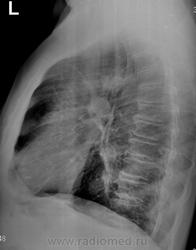

Направлен на рентгенографию ОГК с подозрением на пневмонию

Через 10 дней после проведения противовоспалительной терапии.

уж больно грубая деформация рисунка для инфильтрации?! ателектаз верхушечных сегментов по обзорным снимкам и доп. тень в области головки корня, в/долевой бронх не могу проследить монитор не позволяет наверное.

Я о субсегментарном ателектазе  в S 2 думаю. Бронхоскопию бы. Но сначала - АРХИВ!!!

Левый корень уплотнен, расширен за счет головки, ателектаз С 2, динамики нет. Думаю, более вероятно образование. Интересен анамнез, иначе зачем бы его лечили 2 нед а\б.